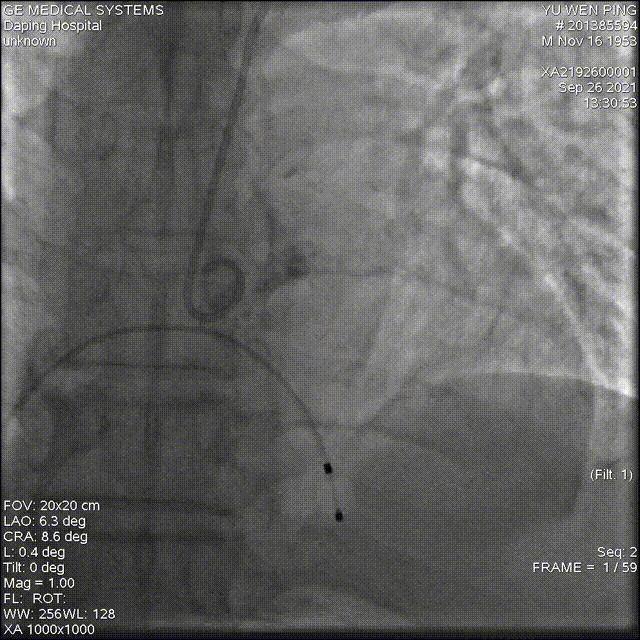

以 Seldinger法穿刺右桡动脉,行PCI后,使用PIG造影管行主动脉根部造影

造影确定输送器位置

高位释放瓣膜